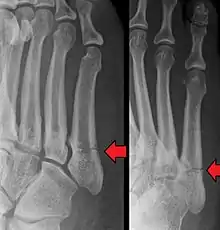

Differential diagnosis

- Proximal diaphysis, typically stress fracture.[12][13]

- Metaphysis: Jones fracture[14]

-Tuberosity: Pseudo-Jones fracture[15] (avulsion fracture).[15]

Other proximal fifth metatarsal fractures exist, although they are not as problematic as a Jones fracture. If the fracture enters the intermetatarsal joint, it is a Jones fracture. If, however, it enters the tarsometatarsal joint, then it is likely an avulsion fracture caused by pull from the fibularis brevis tendon. An avulsion fracture at the base of the fifth metatarsal is sometimes called a "dancer's fracture" or a "pseudo Jones fracture", and usually responds readily to non-operative treatment.[18] The X-ray appearance of the developmental "apophysis" in this area may have some resemblance of a fracture, but is not a fracture; it is the secondary ossification center of the metatarsal bone. It is a normal finding that occurs at this site in adolescents.[19] If an injury to that area has occurred, the physician is often able to interpret certain radiographic clues to make the differentiation. An avulsion fracture at this location is typically extra-articular and oriented transversally as compared to the longitudinal orientation of an unfused apophysis.[19]